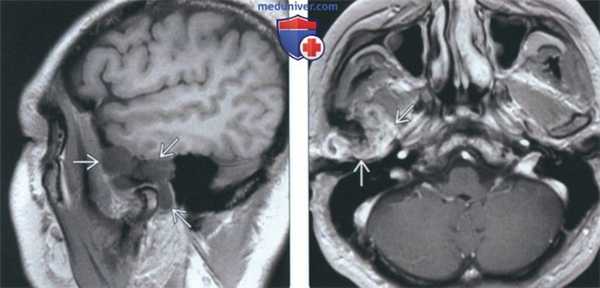

(Слева) На аксиальной КТ без КУ определяется ХС правого мыщелка, снаружи от которого видны множественные плотные включения в отсутствие явного объемного образования. Внутренний край мыщелка склерозирован. Обратите внимание, насколько правый мыщелок отличается от неизмененного левого.

(Справа) На корональной реформатированной КТ без КУ у этого же пациента в мягких тканях визуализируется кольцевидный кальцинат с гиподенсным центром. Определяется деструкция стенок суаавной ямки и большого крыла клиновидной кости. Мыщелок увеличен.

(Слева) На сагиттальной МРТ (Т1 ВИ) у этого же пациента вокруг мыщелка визуализируется многокамерное объемное образование, вовлекающее суставную ямку и большое крыло клиновидной коои.

(Справа) На аксиальной MPT (Т1 ВИ С+ FS) у этого же пациента определяется обширное контрааное усиление солидного объемного образования, окружающего мыщелок, что позволяет исключить его воспалительный характер.